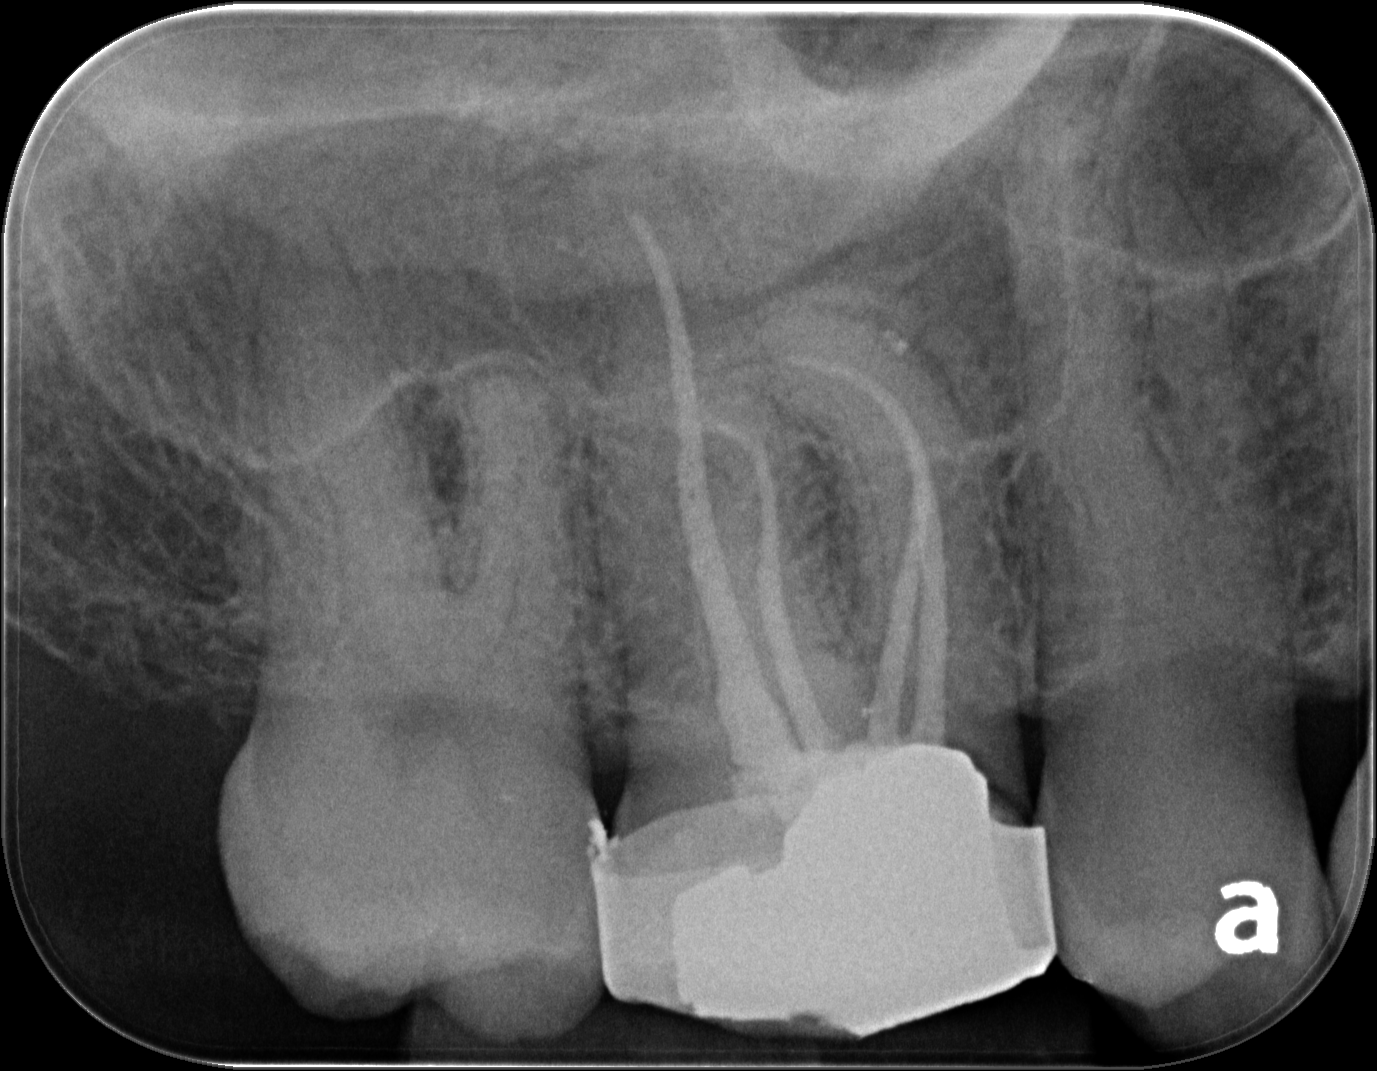

nice root filling3.PNG